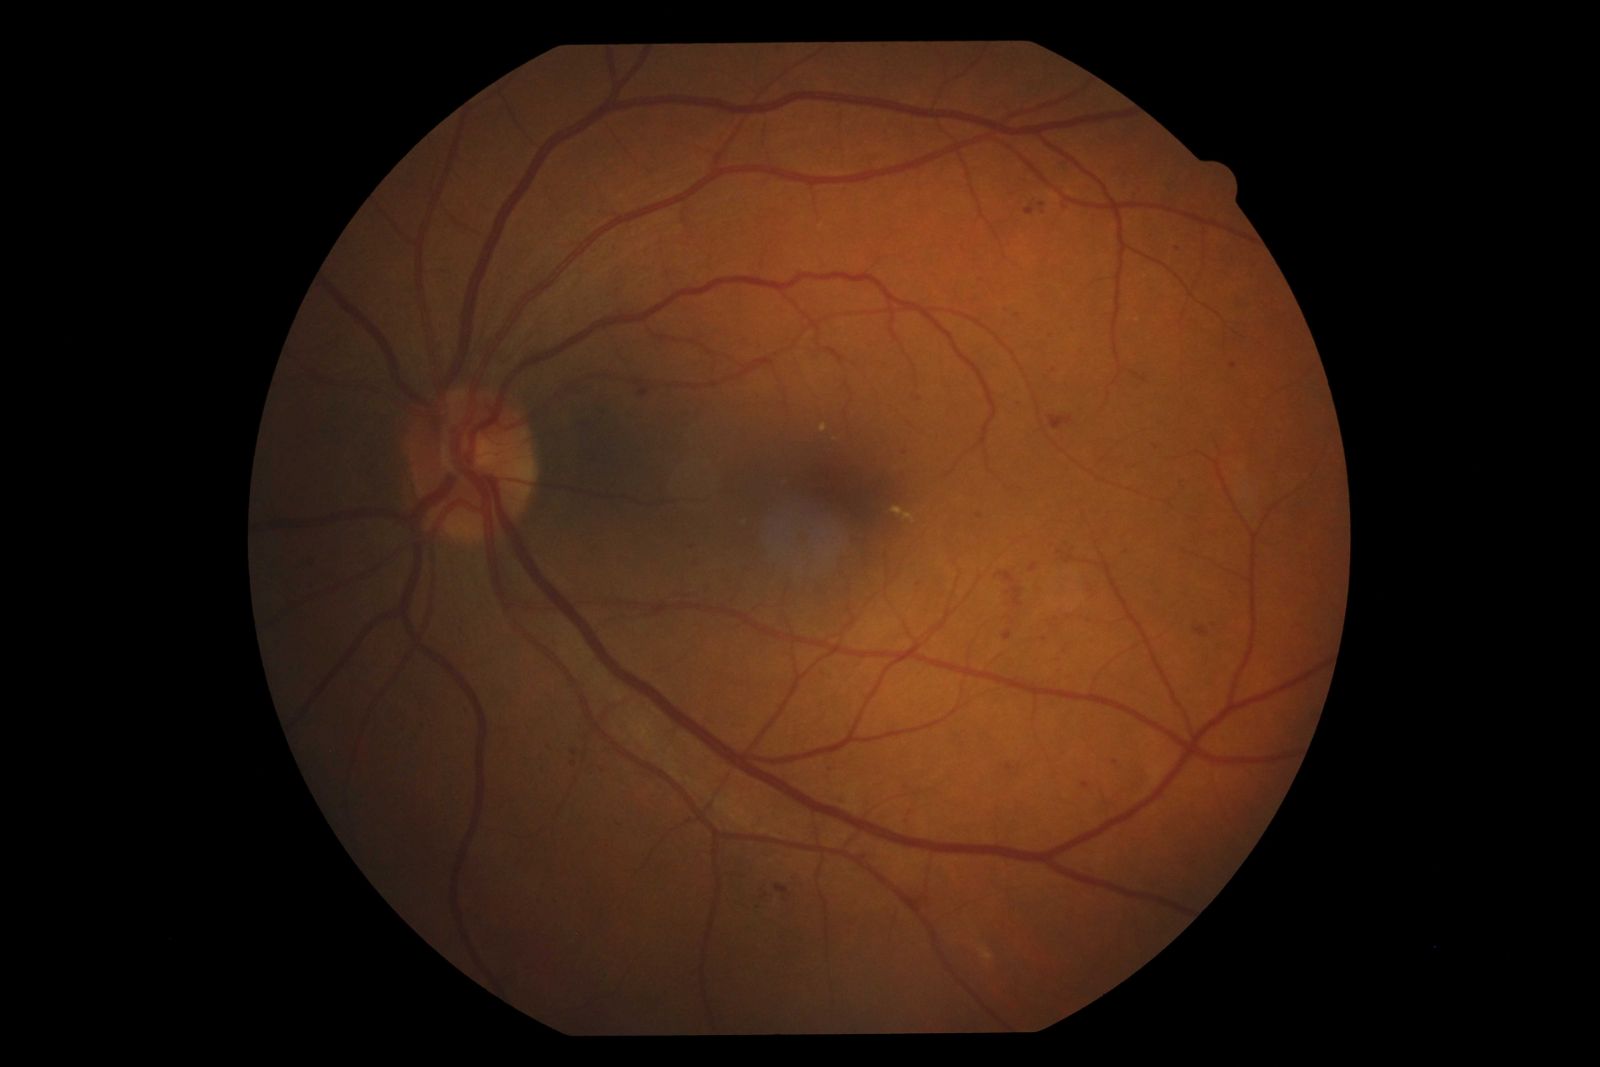

Contudo, independente do tempo de doença, quando o diabetes não esta controlado, a hiperglicemia desencadeia várias alterações no organismo, como aumento do fator de crescimento endotelial vascular (VEGF), danos na estrutura do DNA e de outros componentes celulares e da inflamação crônica. Essas alterações lesam os vasos sanguíneos e aumentam a permeabilidade vascular da retina, o que pode levar ainda à formação do edema macular diabético (figura abaixo).

A RD não proliferativa é o estagio menos avançado da doença, podendo apresentar microaneurismas, hemorragias e vasos sanguíneos obstruídos, que podem fazer com que diversas áreas da retina fiquem sem suprimento de sangue com oxigênico e nutrientes (isquemia). Estas áreas isquêmicas podem estimular a formação de novos vasos sanguíneos (neovasos), evoluindo então para a retinopatia proliferativa.

Na retinopatia diabética proliferativa, a doença é caracterizada pelo aparecimento de novos vasos sanguíneos (neovasos), devido à presença de áreas isquêmicas, com impedimento do fluxo sanguíneo adequado. Esses neovasos são frágeis e crescem ao longo da retina sem causar qualquer sintoma visual. No entanto, eles podem romper e liberar sangue (hemorragia) (fig. abaixo), provocando perda de visão grave de forma súbita e até mesmo cegueira. Entre as razões para a perda de visão na RD profliferativa, alem da hemorragia vítrea, estão o descolamento de retina e o glaucoma neovascular.

Na retinopatia diabética, a principal causa de baixa acuidade visual é o edema macular, acometendo cerca de 30% dos pacientes com mais de 20 anos de doença.